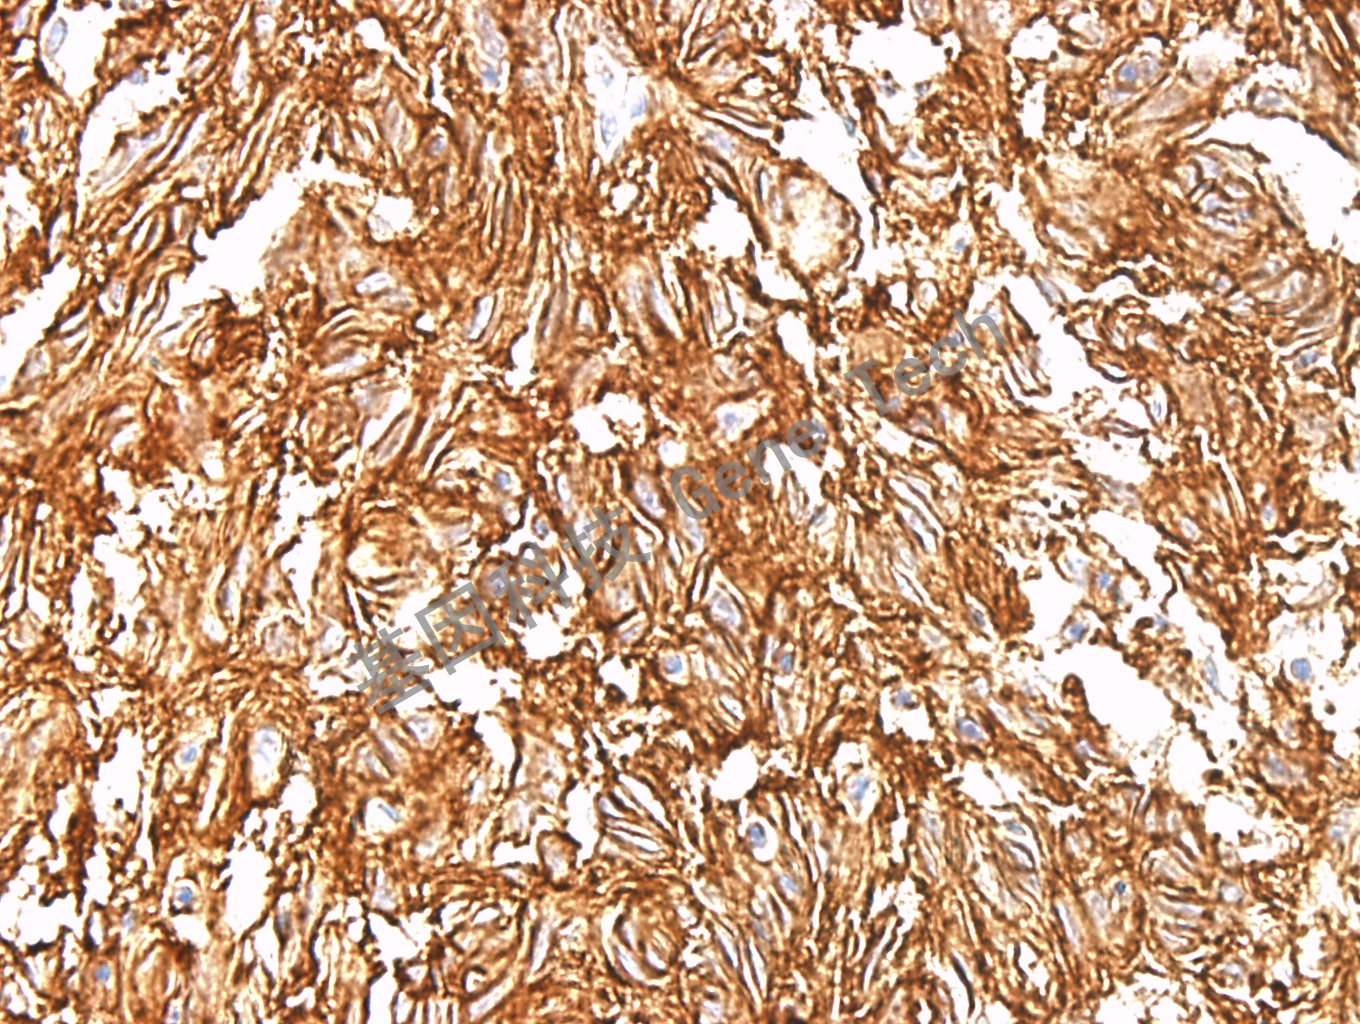

胃间质瘤石蜡切片,用 DOG1(GT2054)染色,细胞膜/细胞浆阳性,DAB 显色。

DOG-1(Discovered on GIST-1)是一种在胃肠间质瘤中特异表达的细胞膜表面蛋白。功能尚不是十分清楚的蛋白,但可以选择性的在胃肠间质瘤中表达。约87%的胃肠间质瘤可以表达DOG1。偶尔表达于滑膜肉瘤、平滑肌肉瘤等。在胃肠间质瘤的诊断中与CD117相互补充。